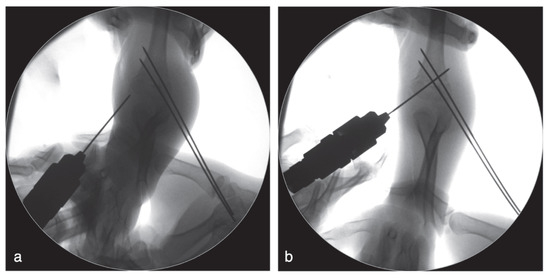

A Modified Technique for Medial Pin Placement in Pediatric Supracondylar Humerus Fractures

by Zhi-Kang Yao, Li-Kai Kuo and Wei-Ning Chang

Surg. Tech. Dev. 2025, 14(4), 36; https://doi.org/10.3390/std14040036 - 21 Oct 2025

Background: Displaced pediatric supracondylar humerus fractures (PSHFs) commonly require surgical treatment. Medial pin placement can cause iatrogenic ulnar nerve injury. This study presents a modified, step-by-step cross-pinning technique for PSHFs designed to avoid iatrogenic ulnar nerve injury. Methods: We retrospectively included [...] Read more.

Background: Displaced pediatric supracondylar humerus fractures (PSHFs) commonly require surgical treatment. Medial pin placement can cause iatrogenic ulnar nerve injury. This study presents a modified, step-by-step cross-pinning technique for PSHFs designed to avoid iatrogenic ulnar nerve injury. Methods: We retrospectively included patients with PSHF (Gartland types III or IV) who underwent closed reduction and percutaneous cross-pinning at our hospital from June 2014 to December 2024. Demographic data, fracture type, and preoperative and postoperative neurological deficits were recorded. Results: A total of 40 patients (16 boys and 24 girls) with a mean age of 6.6 ± 2.2 years (range, 2–14) were included. Most injuries were type III (35/40; 87.5%), whereas five patients (12.5%) had type IV injuries. Our technique resulted in no new cases of postoperative ulnar neuropathy. Conclusions: This study describes a modified medial pin insertion technique for unstable PSHFs. Careful attention to medial pin placement can minimize iatrogenic ulnar nerve injury. Full article